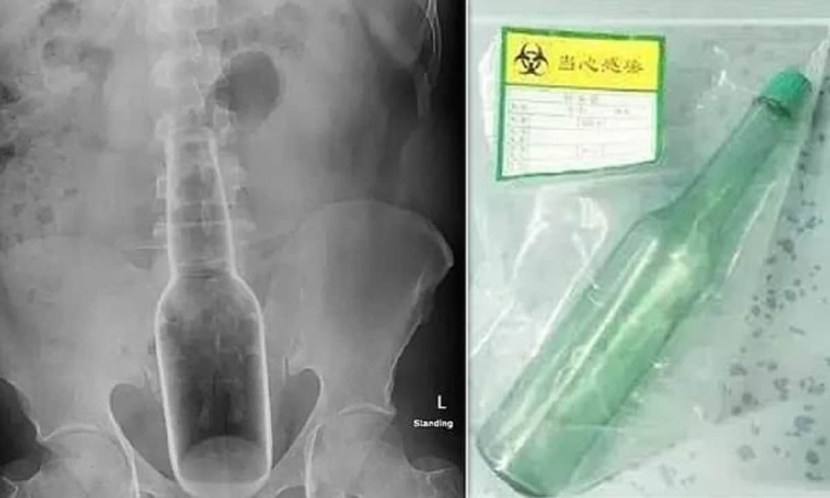

Rectum objects